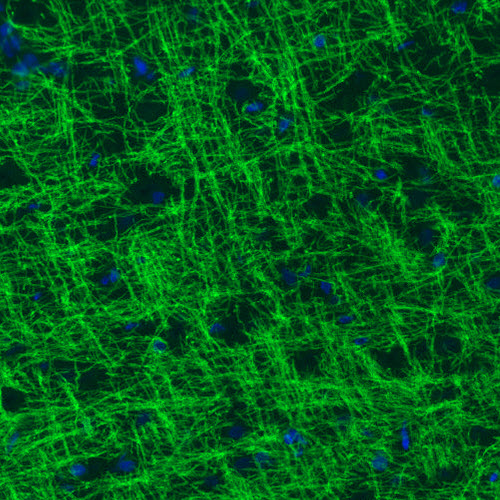

Immunofluorescence staining of rat brain shows strong positivity in myelinated neural fibers in the cerebral cortex.